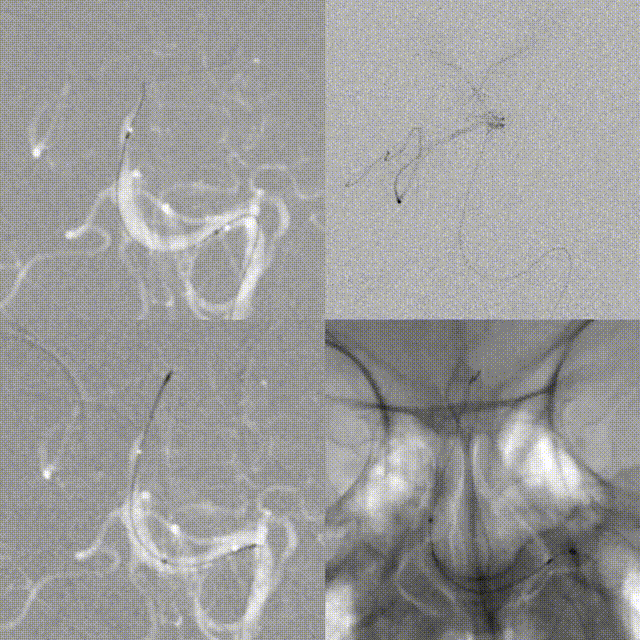

After deployment of Zenith Stent Retriever, distal vessel branches reappeared. Post-thrombectomy angiography showed restored antegrade flow, but with residual severe stenosis.

3D DSA evaluation: Poor hemodynamic compensation at the lesion segment. Balloon dilation was considered risky due to inaccessibility and high risk of vessel rupture. Microcatheter was re-advanced across the stenosis. A 3.0 mm × 15 mm non-tapered intracranial stent was deployed slowly.

The stent expanded and apposed well, with good in-stent flow and improved visualization of distal branches.

15-minute follow-up angiography showed stable in-stent flow in the basilar artery